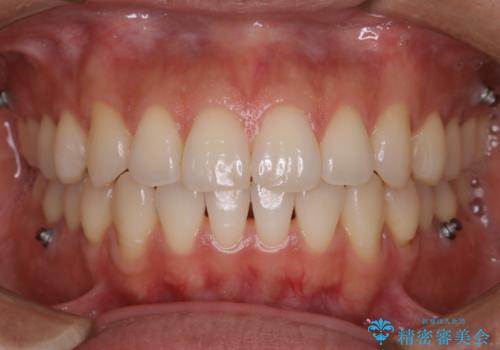

インビザラインの矯正中のクリーニング